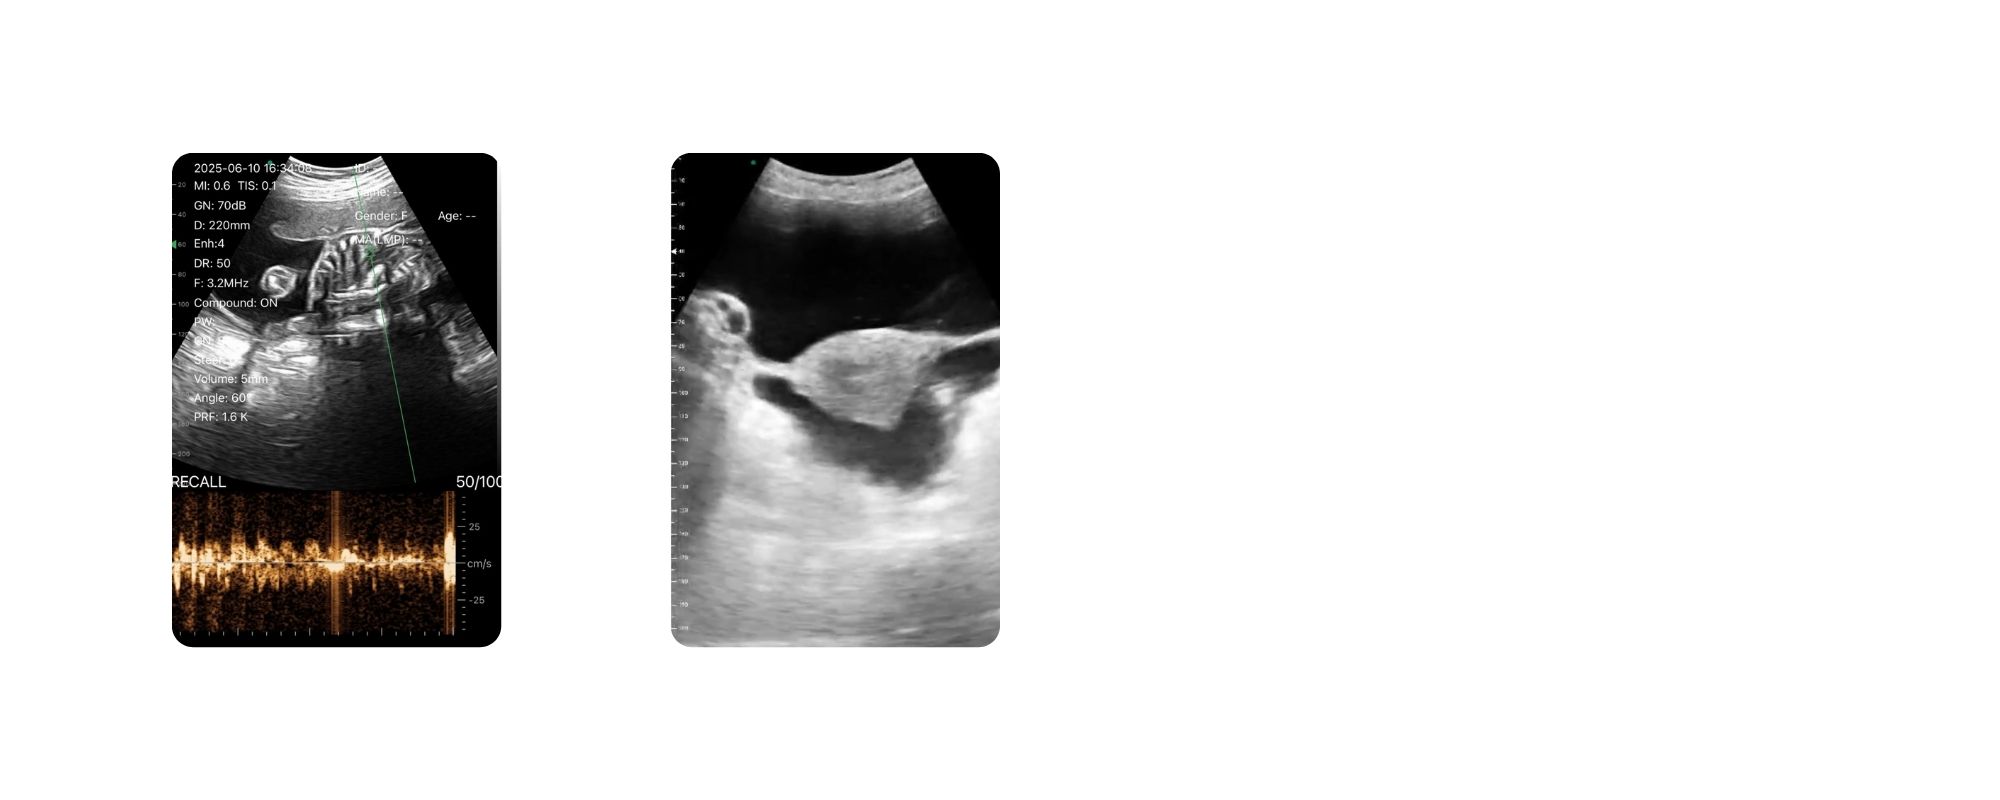

دستگاه سونوگرافی هندهلد مدل C5TC یکی از پیشرفتهترین و محبوبترین انواع سونوگرافی موبایل است که با داشتن دو سر کانوکس (Convex) و واژینال (Transvaginal) در یک پروب، بهعنوان یک دستگاه دو سر حرفهای شناخته میشود. این ویژگی باعث شده که C5TC مورد توجه پزشکان زنان و زایمان، مامایی، ارولوژی و متخصصان تصویربرداری قرار گیرد و در کاربردهای مختلف تشخیصی عملکرد بسیار دقیقی ارائه دهد. دستگاه C5TC تمام مدهای تصویربرداری پزشکی از جمله B/M، Color Doppler، PW Doppler و PDI را پشتیبانی میکند و همچنین مجهز به پریستهای تخصصی مربوط به جنین و زنان است که روند تصویربرداری را سریعتر، دقیقتر و سادهتر میسازد.

با وجود ابعاد بسیار کوچک، کیفیت تصویر C5TC در سطح دستگاههای لپتاپی است و وضوح بالا، نفوذ عمقی و نمایش دقیق بافتها باعث میشود تشخیص کوچکترین ضایعات، ساختارهای جنینی، بافت پروستات و جزئیات رحم با دقت عالی انجام شود. یکی از مهمترین قابلیتهای این دستگاه، اندازهگیری پارامترهای جنینی مانند BPD، HC، AC، FL، تخمین سن بارداری و وزن جنین بشکل خودکار است که فرآیند تشخیص را دقیقتر و سریعتر میکند.

| C5TC | 5CT-CPROBE CT | اندوکویتی /کانوکس | B, B/M, color, PW, PDI imaging | 128 | 3.5-5

6.5-8 |

260 | آبی تیره | R60 |